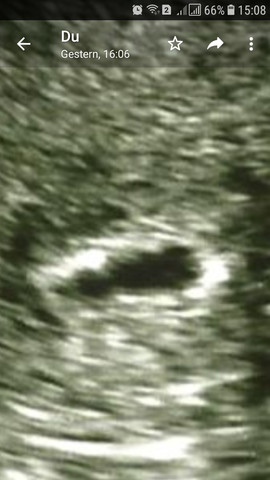

8 ssw ultraschall leere fruchthohle. Wenn sich von alleine nichts tut, kann man auch das Abbluten einleiten oder eine Ausschabung Antwort auf leere fruchthöhle in der 8SSw Hallo, hierzu sind entweder Verlaufskontrollen des Schwangerschaftshormons im Abstand von 23 en notwendig, um zu sehen, ob sich der Wert in etwa verdoppelt oder. SSW auf dem Ultraschall erkennen, sogar mit Herzchen Das ist nur meine Erfahrung, jeder ist individuel Ich hatte auch eine leere Fruchthöhle ob 7 SSW oder 8 SSW, weiß ich leider nicht mehr Eine leere Fruchthöhle in 7 SSW kann vorkommen Soweit ich weiß, sollte man ich ab der 8 etwas sehen. Leere Fruchthöhle in der 7 Ssw 61 Guten , War am Montag beim FA da wurde festgestellt beim Ultraschall, dass ich 6 1 wäre und die Fruchthöhle 11,1 mm ist wo das aber nach meiner Rechnung normal nicht sein kann weil ich später meinen Eisprung hatte normal wäre ich da gewesen 5 4.

Hallo, ich müsste jetzt rechnerisch 76 sein war gestern bei meinen FA zum Ultraschall man hat nur eine leere Fruchthöhle vom 24 mm gesehen und nichts weiter Letze Woche am Donnerstag war die Fruchthöhle nur 19 mm Nun meine Frage Kann es sein das ich einen Ec. 65 leere Fruchthöhle Hallo, gestern bei 65 rechnerisch, war beim Ultraschall nur eine Fruchthöhle zu sehen und ein Hämatom Dann wird es wohl eine Fehlgeburt werden?. Ich bin heute in der 8 ssw und als ich in der 5 Woche war, war mein hcg schon zu niedrig Er ist aber noch angestiegen Zwar immernoch niedrig aber naja Ich war dann bei 61ssw wieder beim FA und man konnte nur eine leere Fruchthöhle erkennen.

Ich bin jetzt in der 9 ssw ( ) Mein letzter Ultraschall war gestern, die Fruchthöhle ist gewachsen, jetzt bei 1,8 cm Leider ist kein Embryo zu sehen, die Fruchthöhle ist schwarz Allerdings wurde auch der HCG Wert gestern gemessen und dieser liegt bei 100 Am 1512 lag er bei 61 Das heißt ja das er genauso gestiegen ist wie er soll !. Laut Rechnung des Artzes müßte ich jetzt in der 8 SSW Woche sein, nur ist in meinem Bauch nur eine leere Fruchthöhle von ca 1,8 mm Ich kann es einfach nicht glauben Ich habe schon eine Tochter. 8 SSW leere Fruchthöhle 19 August 09 um 039 Letzte Antwort 25 August 09 um 857 Hallo ihr lieben, ich lese öfters bei euch mit und heute brauche ich selbst einen rat von euch, denn ich habe ein problem das mich sehr belastet!.

Ist die Fruchthöhle leer, kommt es in den meisten Fällen zu Blutungen und einer Fehlgeburt Vorher ist man trotzdem schwanger und hat trotzdem Schwangerschaftssymptome Der HCG steigt Treten die Blutungen nicht ein, wird die leere Fruchthöhle in der 5 SSW, 6SSW, 7 SSW oder 8 SSW von einem Frauenarzt beim Ultraschall festgestellt. Hallo, ich bin aktuell in der 8 SSW (76) Bei meiner letzten Ultraschall Untersuchung vor 4 en, konnte man nur eine leere Fruchthöhle sehen Meine Frauenärztin meinte darauf hin, dass ich mich auf eine nicht intakte Schwangerschaft einstellen soll Nach drei Minuten war der Ultraschall dann beendet und es wurden nichts weiters mehr gemacht. 8ssw und leere fruchthöhle?.

Guten , ich bin aktuell in der 8 SSW (75) Bei meiner letzten Ultraschall Untersuchung vor drei en, konnte meine Frauenärztin nur eine leere Fruchthöhle erkennen Sofort sagte sie mir nach 3 Minuten schon, dass ich von einer nicht intakten Schwangerschaft ausgehen könnte. Rein rechnerisch müsste ich schon in der 8 SSW sein, habe am den ersten tag meiner regel gehabt. Natürlich hoffe ich mit dir, dass sich doch noch etwas zeigt, und damit du ein besseres Gefühl hast, kannst du ja noch abwarten, sofern die Ärzte nichts finden, das dagegen spricht!.

In der 8 SSW ist der Embryo in Ihrem Bauch 6 Wochen alt Die Differenz zwischen Hallo, ich bin aktuell in der 8 SSW (76) Bei meiner letzten Ultraschall Untersuchung vor 4 en, konnte man nur eine leere Fruchthöhle sehen Meine Frauenärztin meinte darauf hin, dass ich mich auf eine nicht intakte Schwangerschaft einstellen soll. Ich kann Dich vollkommen verstehen mit Deiner Angst um die leere Fruchthöhle 7 SSW ist ja noch recht früh, bis zur 8 und 9 kann sich noch einiges tun auch wenn es nur 2 Wochen sind Dann hörst Du beim nächsten Termin auf einmal das kleine Herzchen schlagen Ich hatte übrigens auch eine leere Fruchthöhle in der 8 SSW. Ich wäre rechnerische Anfang der 8ssw Jedoch meinte meine FA der ES könnte auch früher gewesen sein Nun erkennt man jedoch seit 2 Wochen nur eine leere Fruchthöhle, die aber stetig gewachsen ist Nur keinen Dottersack oder Embryo Ich habe jetzt Tabletten für den Abgang mitbekommen, die ich nehmen könnte.